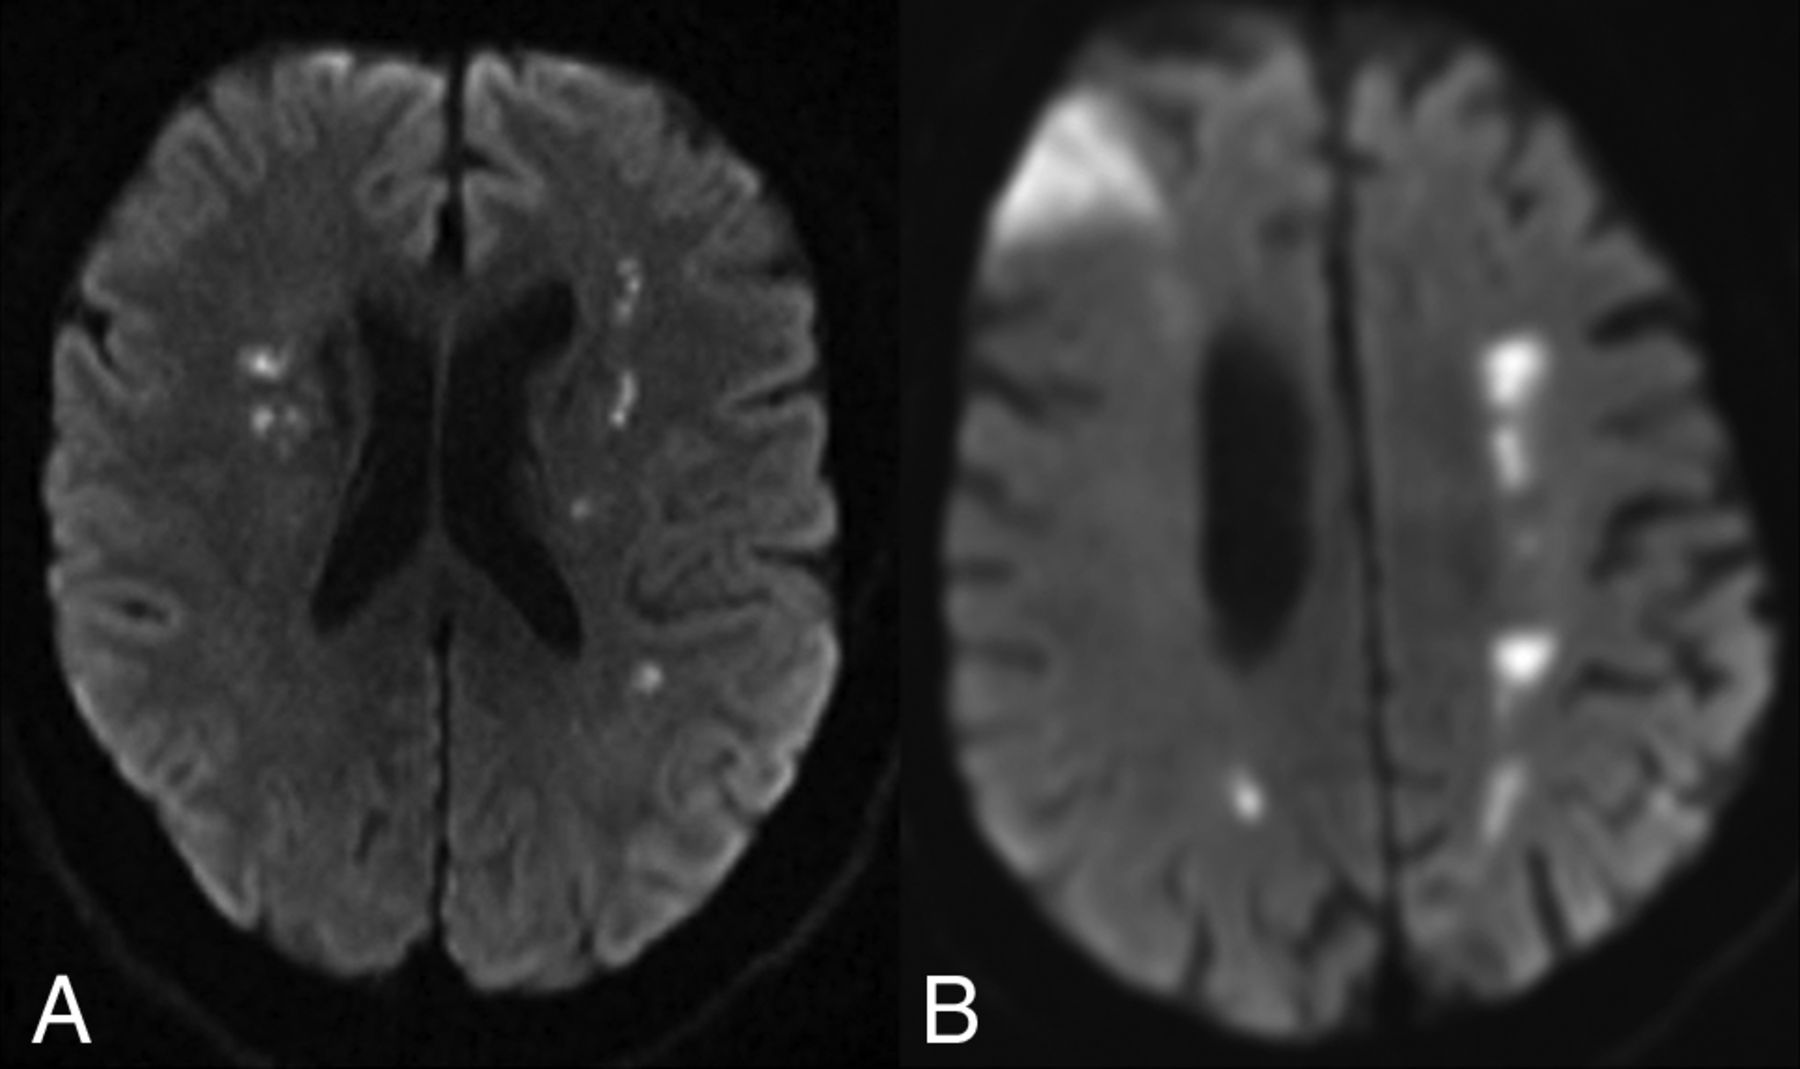

Between March 14 and April 26, 2020, eighty-six patients (48 men, 38 women) with mean age of 67.4 years (range, 25–94 years) met the inclusion criteria with imaging-confirmed infarction (83.7%) or pure intracranial hemorrhage (16.3%) (Fig 1A). Associated intracranial hemorrhage (Fig 1B) was found in 20.8% of 72 patients with infarction, including 9 with simultaneous hemorrhage and infarction and 6 with hemorrhagic transformation, including 1 hemorrhagic venous infarction secondary to dural venous sinus thrombosis (Fig 1C, -D). Multivascular territory infarction (33/72 patients; 45.8%) predominated, including 12 with a watershed pattern (Fig 2), followed by single vascular territory infarction (29/72 patients, 40.3%) and solitary small-vessel occlusion (10/72 patients, 13.9%).

Multivascular territory infarctions in COVID-19. MR imaging of the brain diffusion-weighted imaging demonstrates watershed-pattern infarctions in a 52-year-old man with mild COVID-19 symptoms, who awoke at home with left hemiparesis (A) and an 86-year-old woman admitted for hypoglycemia, dehydration, and COVID-19 pneumonia (B) and found to have new-onset atrial fibrillation; 8 days into her hospitalization, she developed lethargy, left hemiparesis, expressive aphasia, and dysphagia.